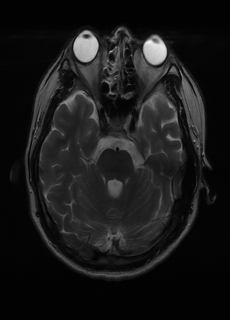

As we observe from the right image in Fig. 2, our BRM, both from MIMO and SISO settings, predicts the performance of dedicated models with a high correlation. We further choose the best three , and perform the last stage of fine-tuning accordingly to (6). A visual evaluation on real data is shown in Fig. 3. For simulated data, please refer to the Supplemental Material section.

Base on the best performing , we perceive that among , , and FLAIR, the results are best when is sampled the most. We suggest that this makes intuitive sense as images provide the best contrast out of the three sequences, which can compensate for the details lost in other images. The same observation can be made on the simulated data, where both and FLAIR show good contrast. When the time setting is changed to non-uniformity, we can see that our search for the best sampling strategy reflects the change. is sampled more as a result of faster acquisition time, while is still sufficiently sampled.

| Sequence | LR | SISO | MIMO | MIMO tuned | GT |

|---|---|---|---|---|---|

(a) 34.38/0.9371

(a) 34.38/0.9371

|

(b) 42.42/0.9883

(b) 42.42/0.9883

|

(c) 44.60/0.9920

(c) 44.60/0.9920

|

(d) 45.50/0.9940

(d) 45.50/0.9940

|

(e) PSNR/SSIM

(e) PSNR/SSIM

|

|

(f) 29.74/0.8903

(f) 29.74/0.8903

|

(g) 36.25/0.9734

(g) 36.25/0.9734

|

(h) 36.42/0.9752

(h) 36.42/0.9752

|

(i) 37.70/0.9832

(i) 37.70/0.9832

|

(j) PSNR/SSIM

(j) PSNR/SSIM

|

|

(k) 39.89/0.9311

(k) 39.89/0.9311

|

(l) 43.94/0.9864

(l) 43.94/0.9864

|

(m) 44.74/0.9883

(m) 44.74/0.9883

|

(n) 45.49/0.9894

(n) 45.49/0.9894

|

(o) PSNR/SSIM

(o) PSNR/SSIM

|